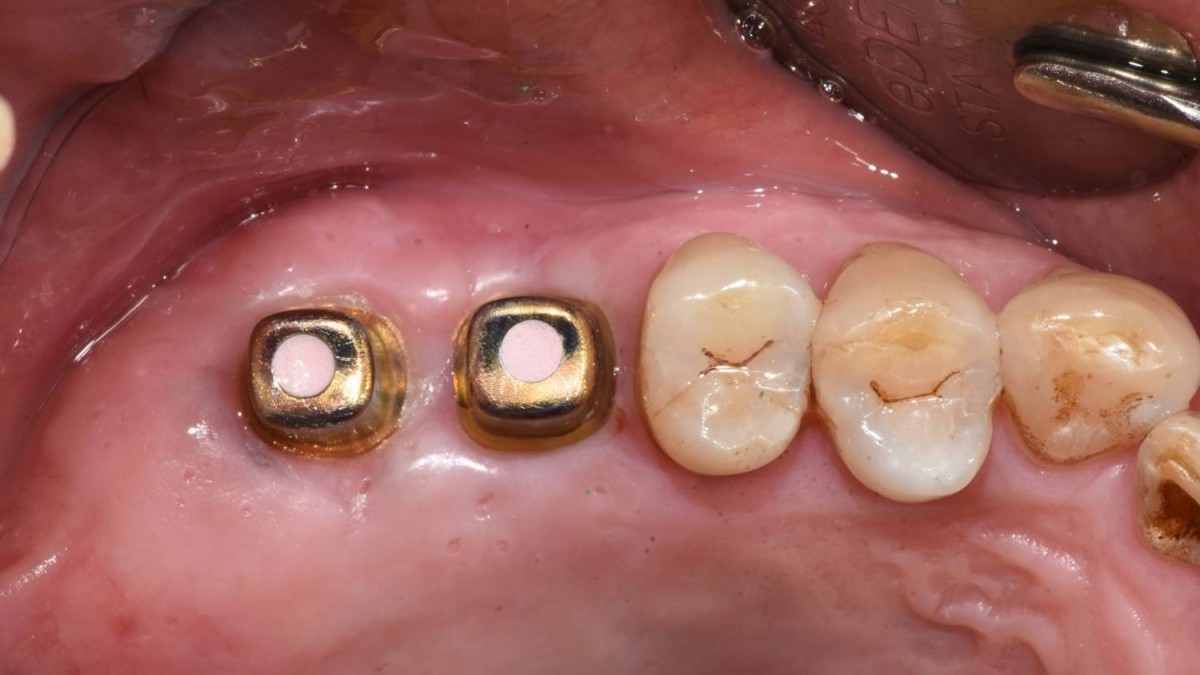

Maxillary Sinus Graft, 2 Implants, Crown Contouring

<GCaks> A 56-year-old male patient had pain-inducing caries, and perio-involved tooth mobility resulted in a tooth fracture at 1st molar. And it was removed months ago. He was a heavy smoker and showed poor oral hygiene.